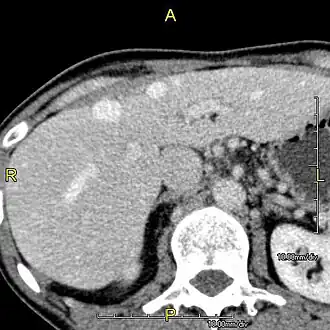

CT scan showing an adult liver in the axial plane

Organogenesis, the development of the organs, takes place from the third to the eighth week during embryonic development. The origins of the liver lie in both the ventral portion of the foregut endoderm (endoderm being one of the three embryonic germ layers) and the constituents of the adjacent septum transversum mesenchyme. In the human embryo, the hepatic diverticulum is the tube of endoderm that extends out from the foregut into the surrounding mesenchyme. The mesenchyme of septum transversum induces this endoderm to proliferate, to branch, and to form the glandular epithelium of the liver. A portion of the hepatic diverticulum (that region closest to the digestive tube) continues to function as the drainage duct of the liver, and a branch from this duct produces the gallbladder.[37] Besides signals from the septum transversum mesenchyme, fibroblast growth factor from the developing heart also contributes to hepatic competence, along with retinoic acid emanating from the lateral plate mesoderm. The hepatic endodermal cells undergo a morphological transition from columnar to pseudostratified resulting in thickening into the early liver bud. Their expansion forms a population of the bipotential hepatoblasts.[38] Hepatic stellate cells are derived from mesenchyme.[39]